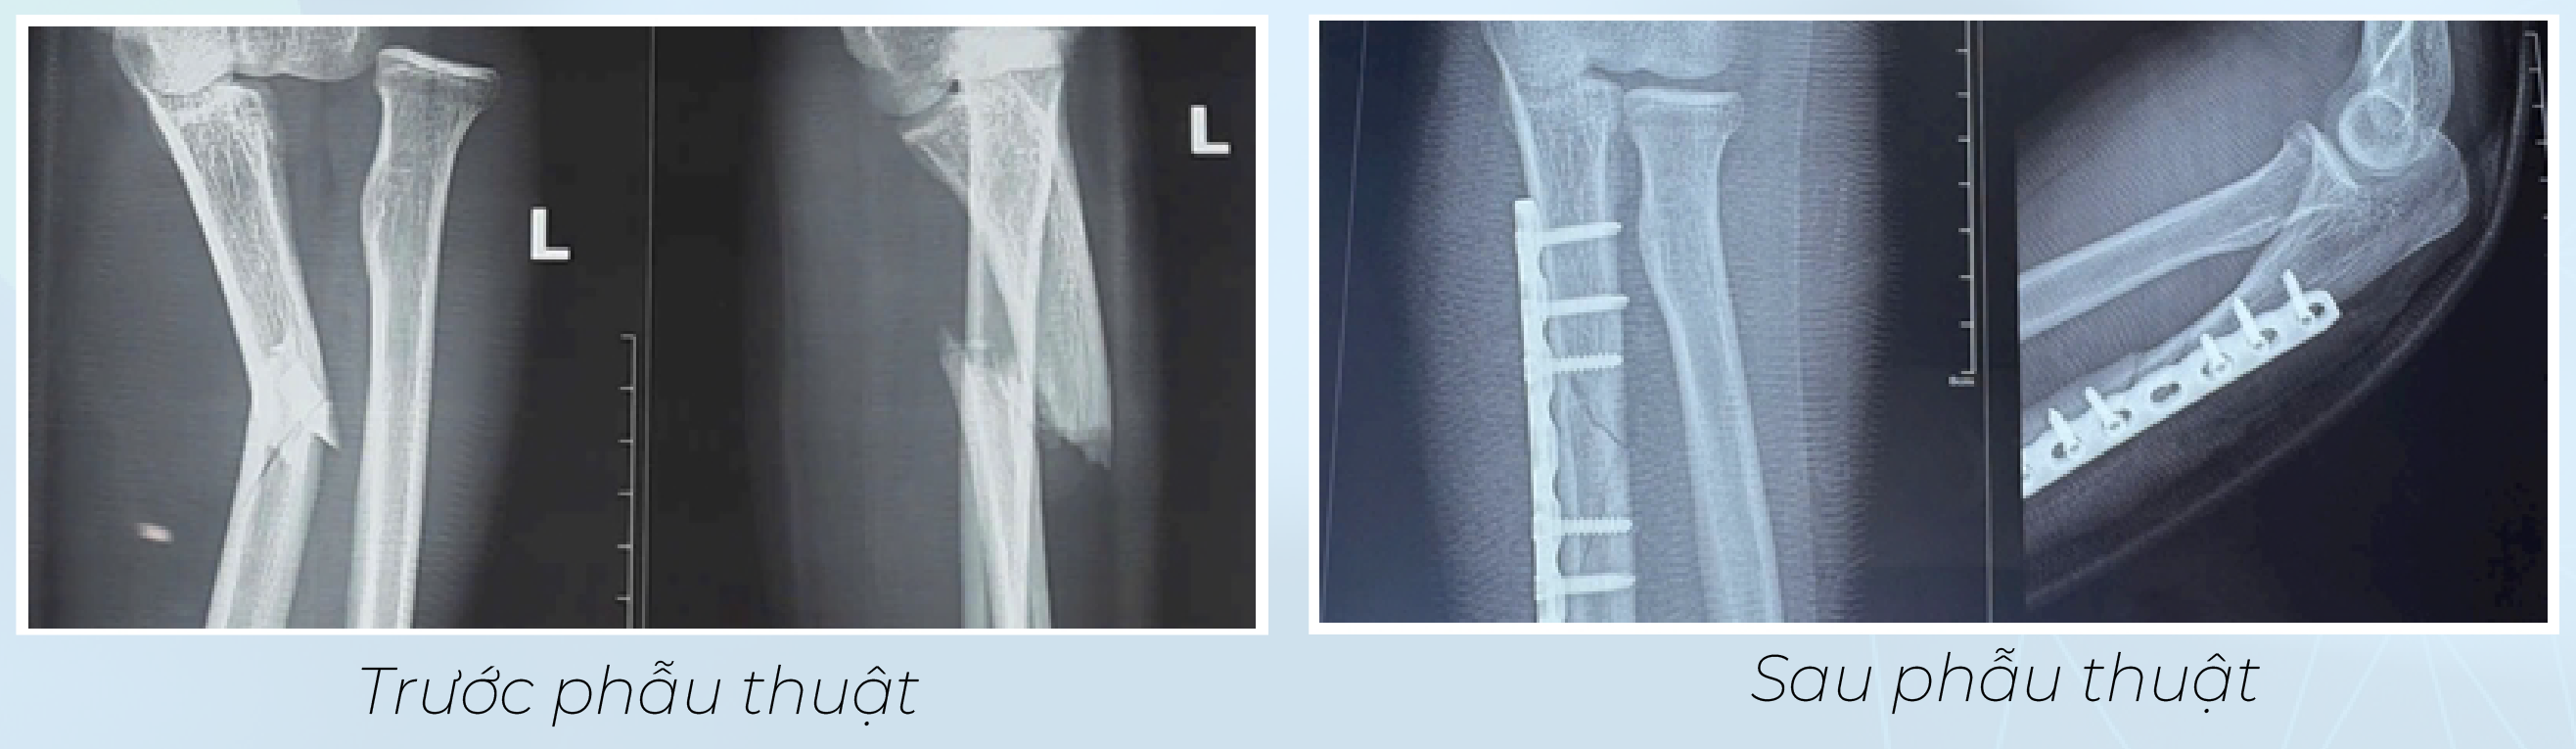

Sáng 16/8/2025, nam công nhân H.V.N (20 tuổi) bị tai nạn lao động rơi từ độ cao khoảng 1,5 mét, nhập viện trong tình trạng đau nhiều vùng cẳng tay trái, hạn chế vận động, liệt duỗi các ngón tay và cổ tay yếu sau chấn thương. Kết quả chẩn đoán hình ảnh cho thấy nam bệnh nhân bị gãy xương cẳng tay dạng Monteggia Bado III, gãy 1/3 trên xương trụ, trật khớp quay trụ trên và tổn thương thần kinh quay.

Trong quá trình phẫu thuật, phẫu thuật viên bộc lộ ổ gãy xương trụ, tiến hành kết hợp xương bằng nẹp vít, nắn chỉnh chỏm quay về vị trí giải phẫu. Đánh giá trong cuộc mổ cho thấy khớp quay – trụ trên vững, không cần mở và khâu lại dây chằng vòng. Ca mổ diễn ra thuận lợi, xương trụ được cố định chắc chắn, chỏm quay trở về vị trí giải phẫu.

Sau phẫu thuật, khớp tay của bệnh nhân vững, không còn trật. Bệnh nhân được bất động cẳng tay tư thế chức năng, theo dõi sát tình trạng thần kinh quay trong 3–6 tháng, đồng thời lên kế hoạch phục hồi chức năng.